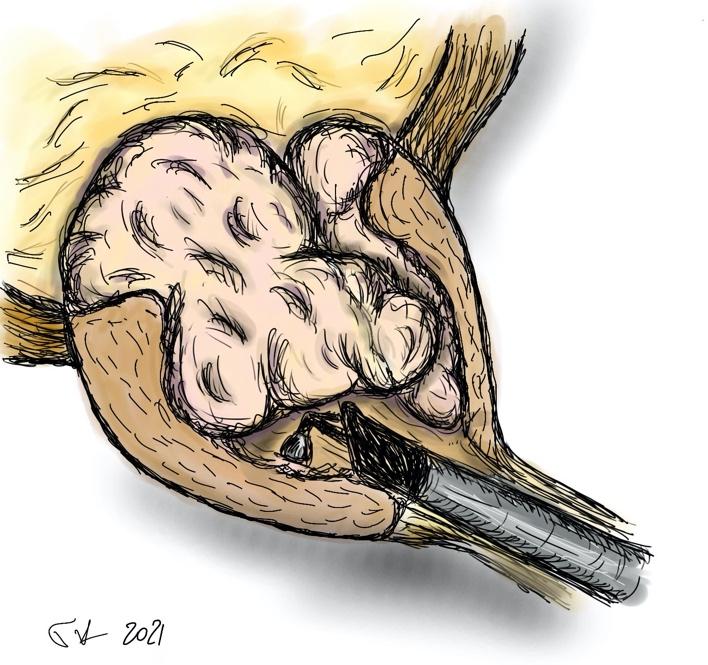

- το αδένωμα έχει πλέον αποκολληθεί από την προστατική κάψα και προωθείται στην ουροδόχο κύστη (εικόνες 5-6)

εικόνες 5-6